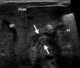

Pylorospasm

Pyloric stenosis is a narrowing of the opening from the stomach to the first part of the small intestine (the pylorus). Symptoms include projectile vomiting without the presence of bile. [Source: Wikipedia ]